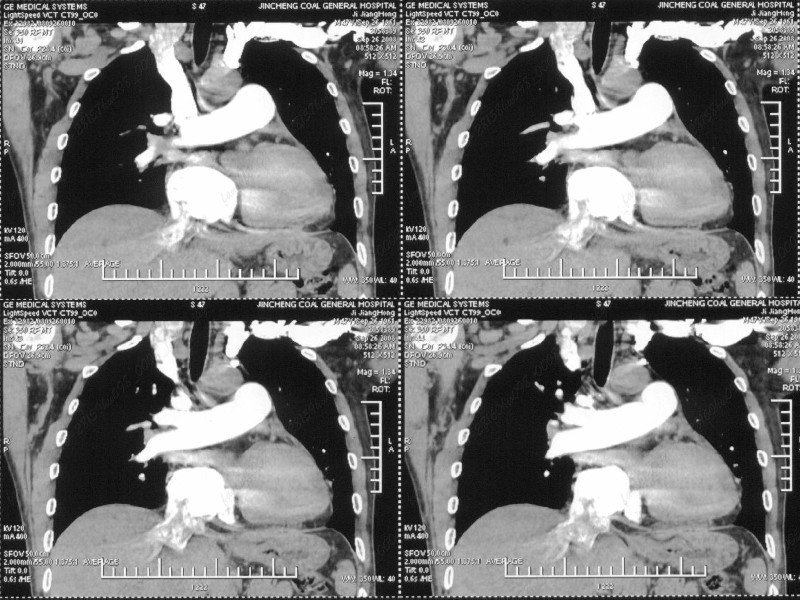

男性,47岁。胸部不适一年,ct检查发现右胸膜下结节。http://www.radida.com/bbs/forum.php?mod=viewthread&tid=46094

汇报临床诊断:右肺动脉分枝栓塞

右肺静脉充盈缺损,左心房体积小,右肺动脉远端动脉充盈缺损,右肺血管影细小,考虑;右肺动脉远端栓塞.